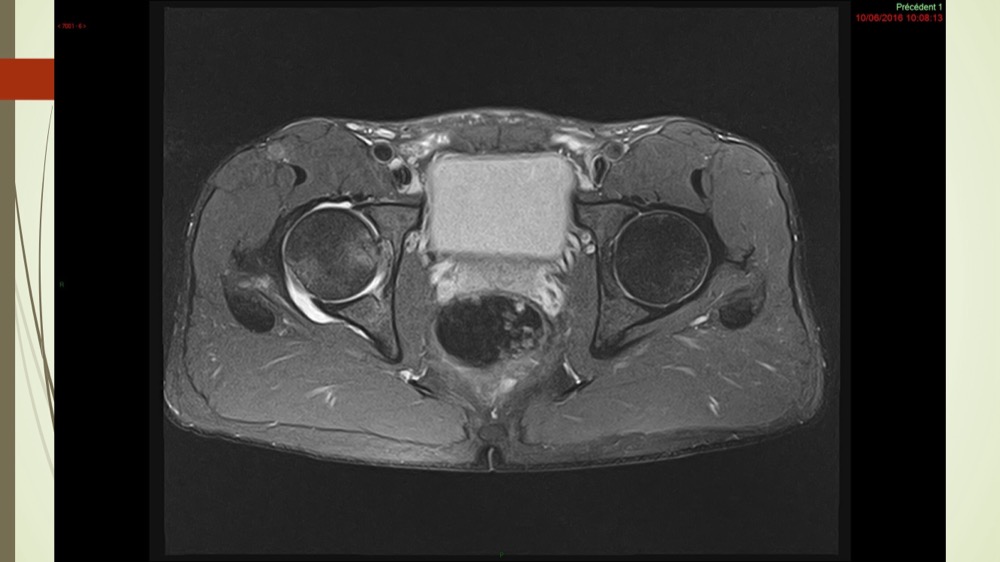

Coxalgie traînante

Kévin Mahé 29/06/2022